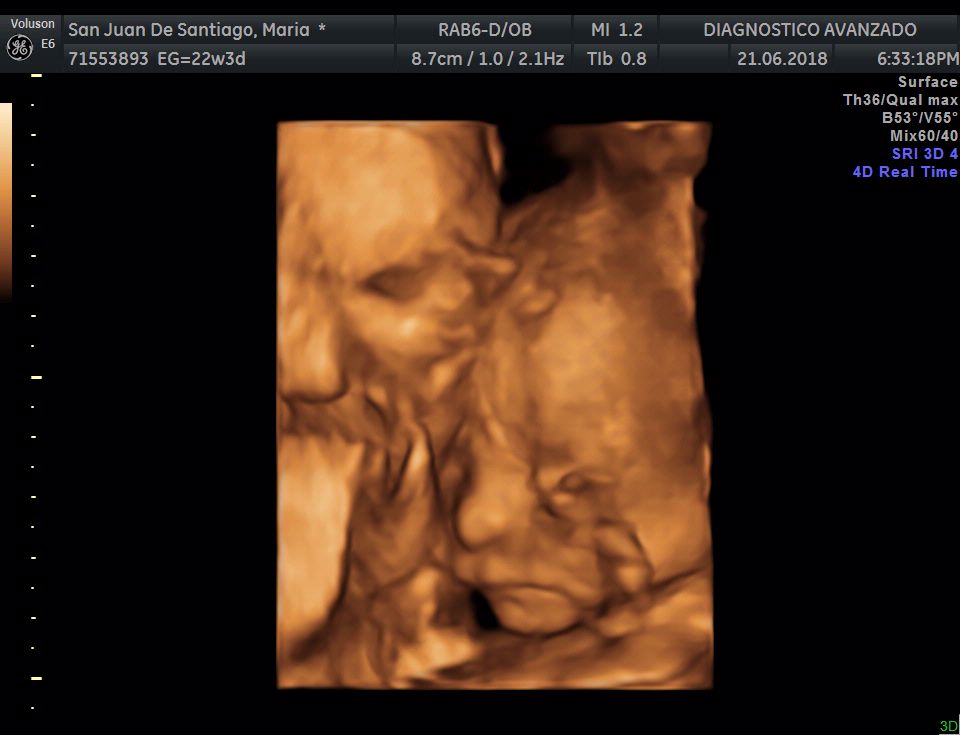

¡Hola a todos! Hoy hemos ido a hacer la tradicional ecografía 3D de la niña, os dejamos todo el material (aunque es un poco demasiado).